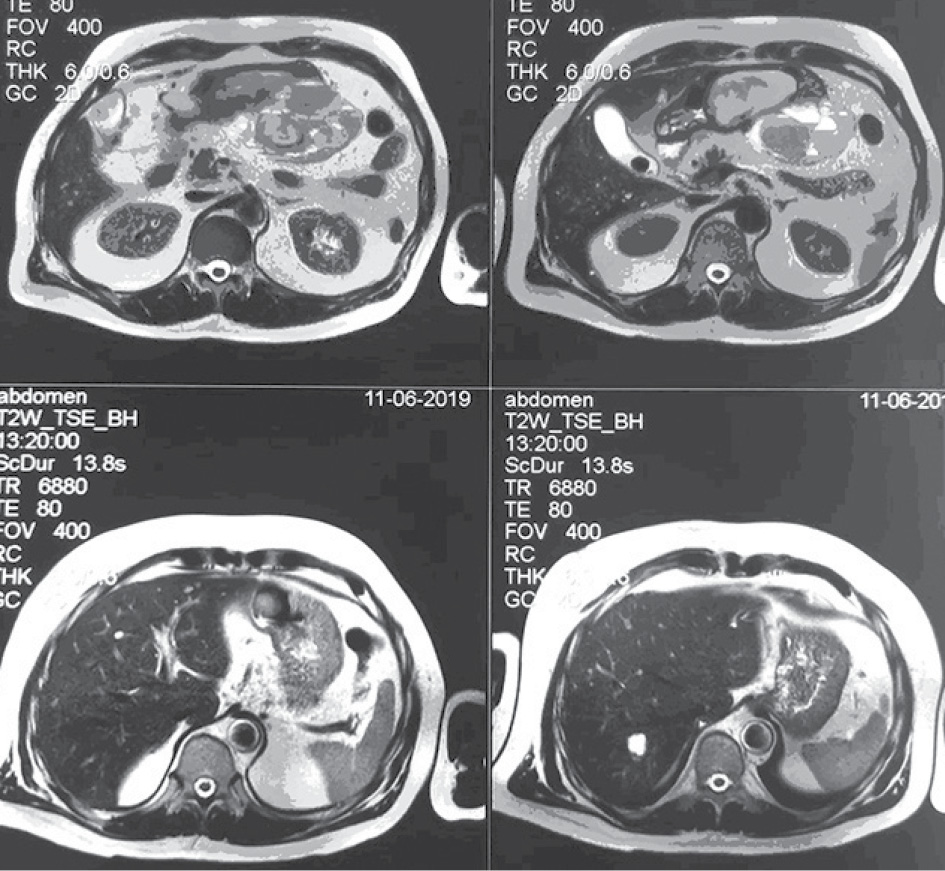

- МРТ с контрастированием от 11.06.2019 г. Заключение: Объёмное образование брюшной полости слева, кистозно-солидной структуры со сдавлением желудка (tumor). Множественные кисты обеих долей печени. Конкремент желчного пузыря. Увеличенные забрюшинные лимфатические узлы (рис. 1–4).

Рис. 1. Увеличенные забрюшинные лимфатические узлы

Рис. 2. Увеличенные забрюшинные лимфатические узлы

Рис. 3. Увеличенные забрюшинные лимфатические узлы

Рис. 4. Увеличенные забрюшинные лимфатические узлы